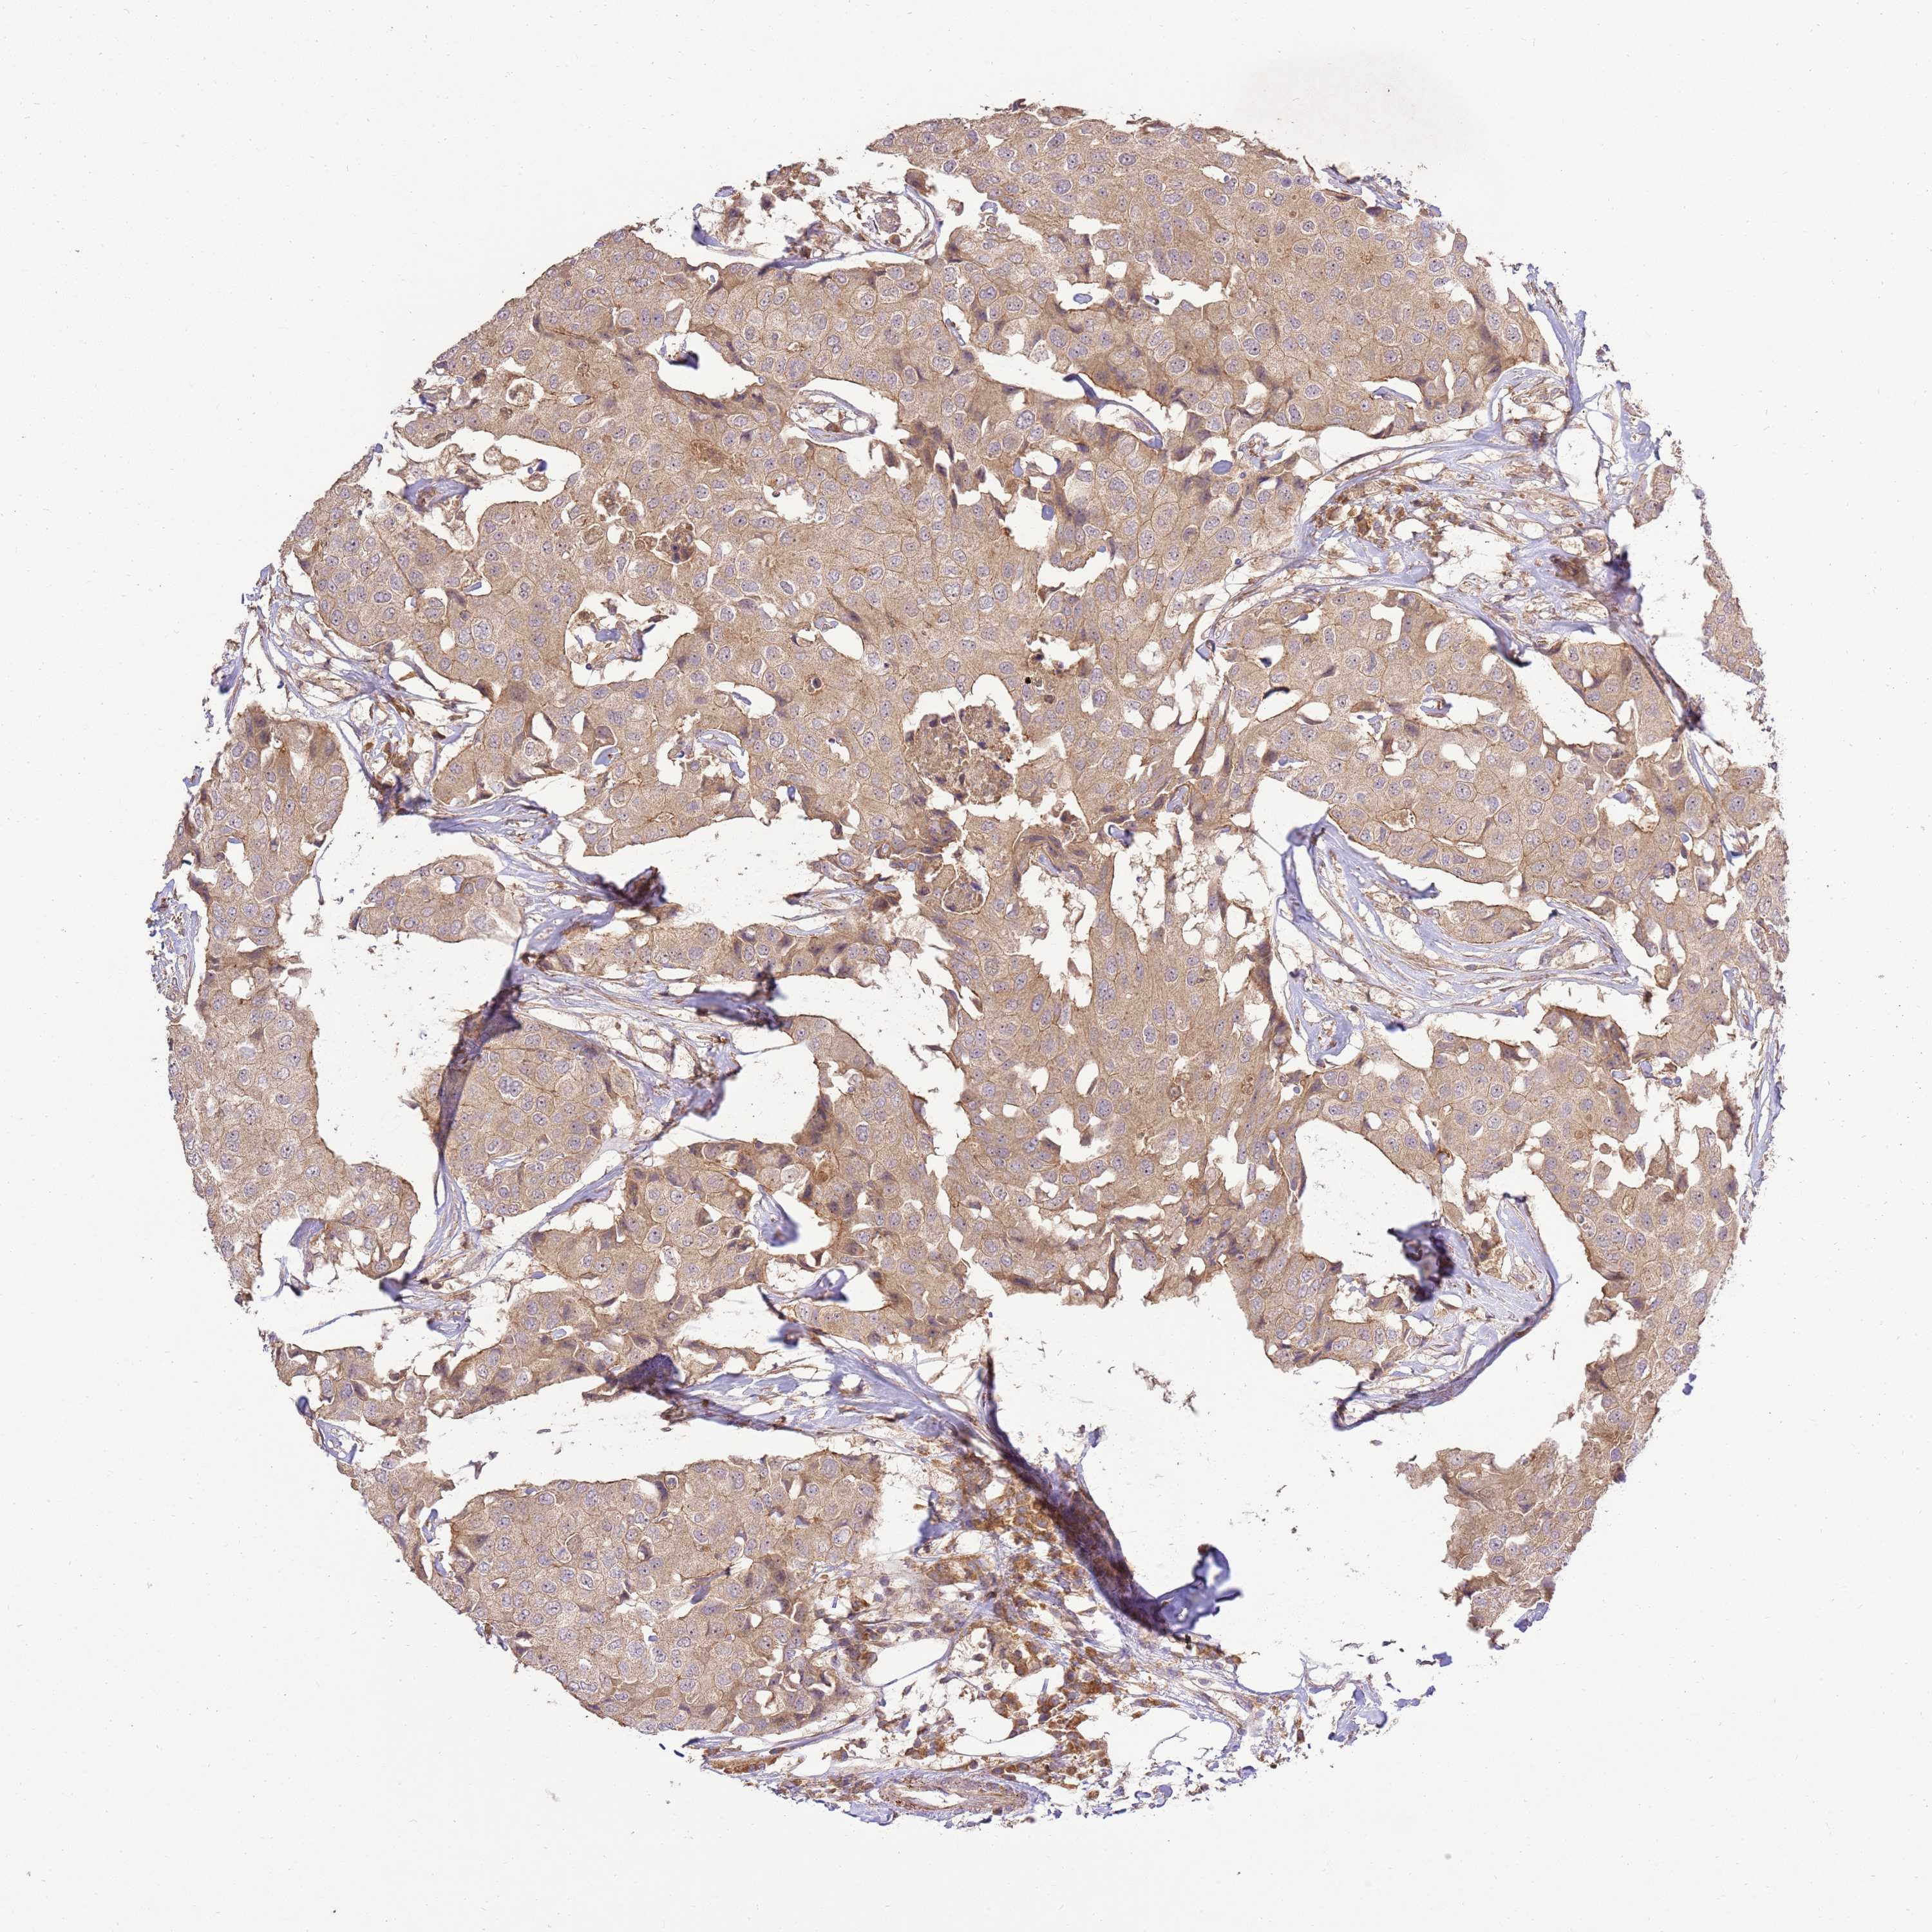

CANCER BREAST CANCER Show tissue menu

BRCA TCGA BRCA VALIDATION PROTEIN EXPRESSION

Average pTPM 3.7